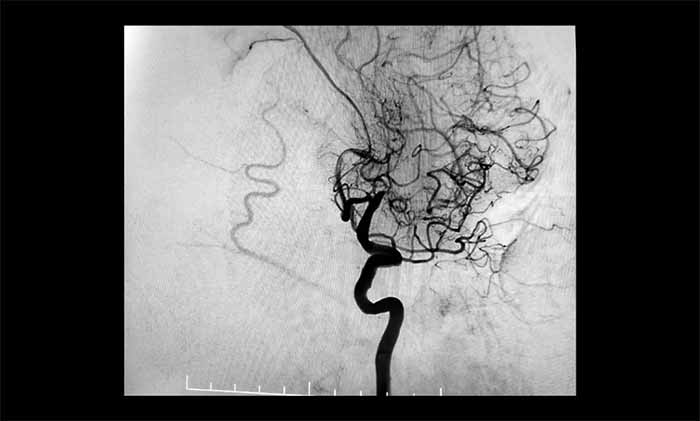

近日,一位70多岁患者因反复出现右侧肢体无力、言语含糊、口角流涎,被诊断为左侧大脑中动脉完全闭塞。他还合并颈内动脉动脉瘤、椎动脉狭窄等复杂问题,手术难度极高。其中,左侧大脑中动脉M1段的慢性完全性闭塞,是导致其神经功能缺损反复加重的主要原因。

席刚明教授、王贵平博士团队经过全面评估,最终在全麻下精细操作,利用微导丝穿过闭塞段,并以“球囊扩张+支架置入”完成血管再通,为患者打通这条关键的“生命线”。术后患者血流通畅,恢复良好。

▲ 左侧大脑中动脉完全闭塞